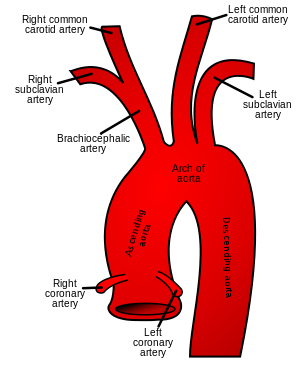

|

Normal anatomical locations of right and left subclavian arteries | |

Aberrant subclavian artery, or aberrant subclavian artery syndrome, is a rare anatomical variant of the origin of the right or left subclavian artery. This abnormality is the most common congenital vascular anomaly of the aortic arch.

The aberrant artery usually arises just distal to the left subclavian artery and crosses in the posterior part of the mediastinum usually behind the oesophagus on its way to the right upper extremity. Such course of this aberrant vessel may cause a vascular ring around the trachea and oesophagus. Dysphagia due to an aberrant right subclavian artery is termed dysphagia lusoria. Palsy of the recurrent laryngeal nerve is termed Ortner's syndrome.

The aberrant right subclavian artery frequently arises from a dilated segment of the proximal descending aorta, the so-called Diverticulum of Kommerel (which was named for the German Radiologist, Burckhard Freidrich Kommerel (1901–1990), who discovered it in 1936). It is alternatively known as lusorian artery.